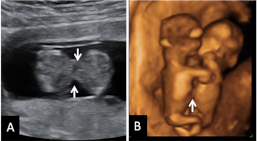

Doppler pulsado en la válvula tricúspide. Registro normal (imagen A) y registro con insuficiencia (imagen B con flechas).